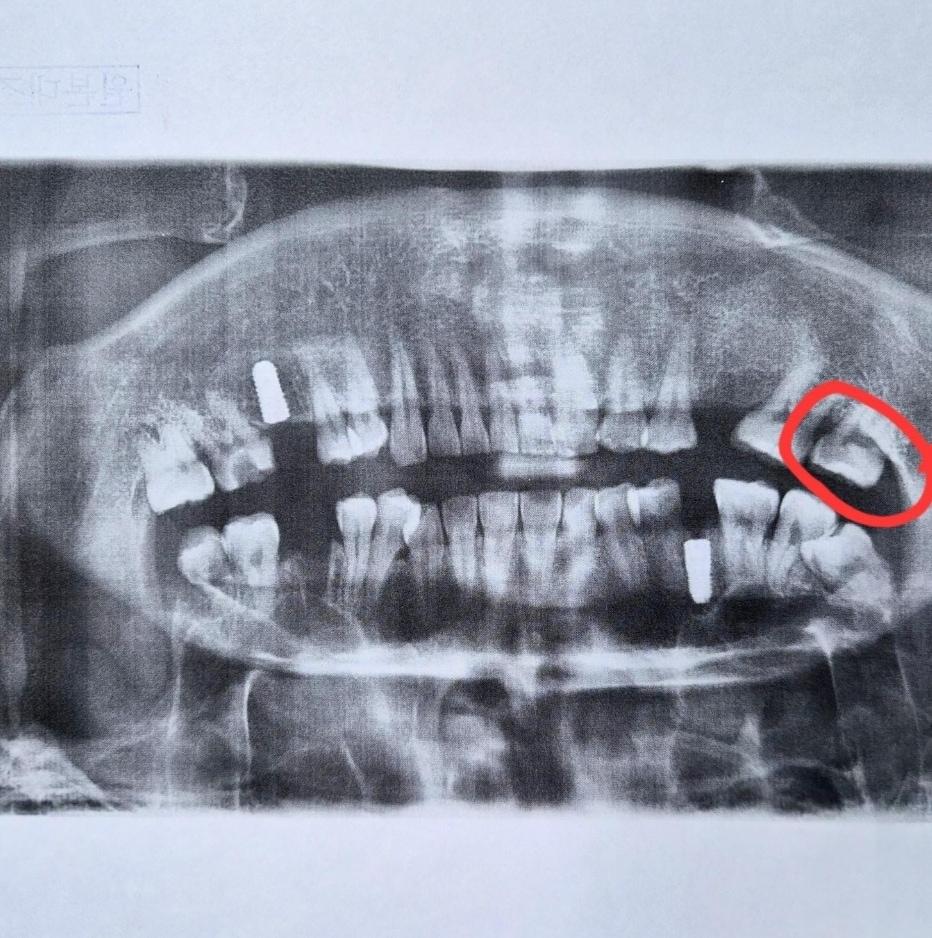

"치과서 다른 치아 잘못 깎아 발치 위기"…인지 기능 장애 환자의 호소